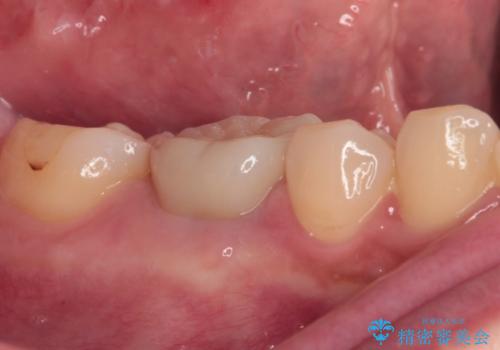

- 奥歯のクラウンが外れたままにしているとのことで来院された患者様です。

奥歯に特に症状はなかったのですが、排膿路が歯肉に認められたため、根管治療を行った上でオールセラミッククラウンにて補綴治療を行うこととしました。